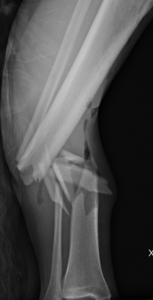

Knee fracture (distal femur, patella, and tibial plateau fractures)